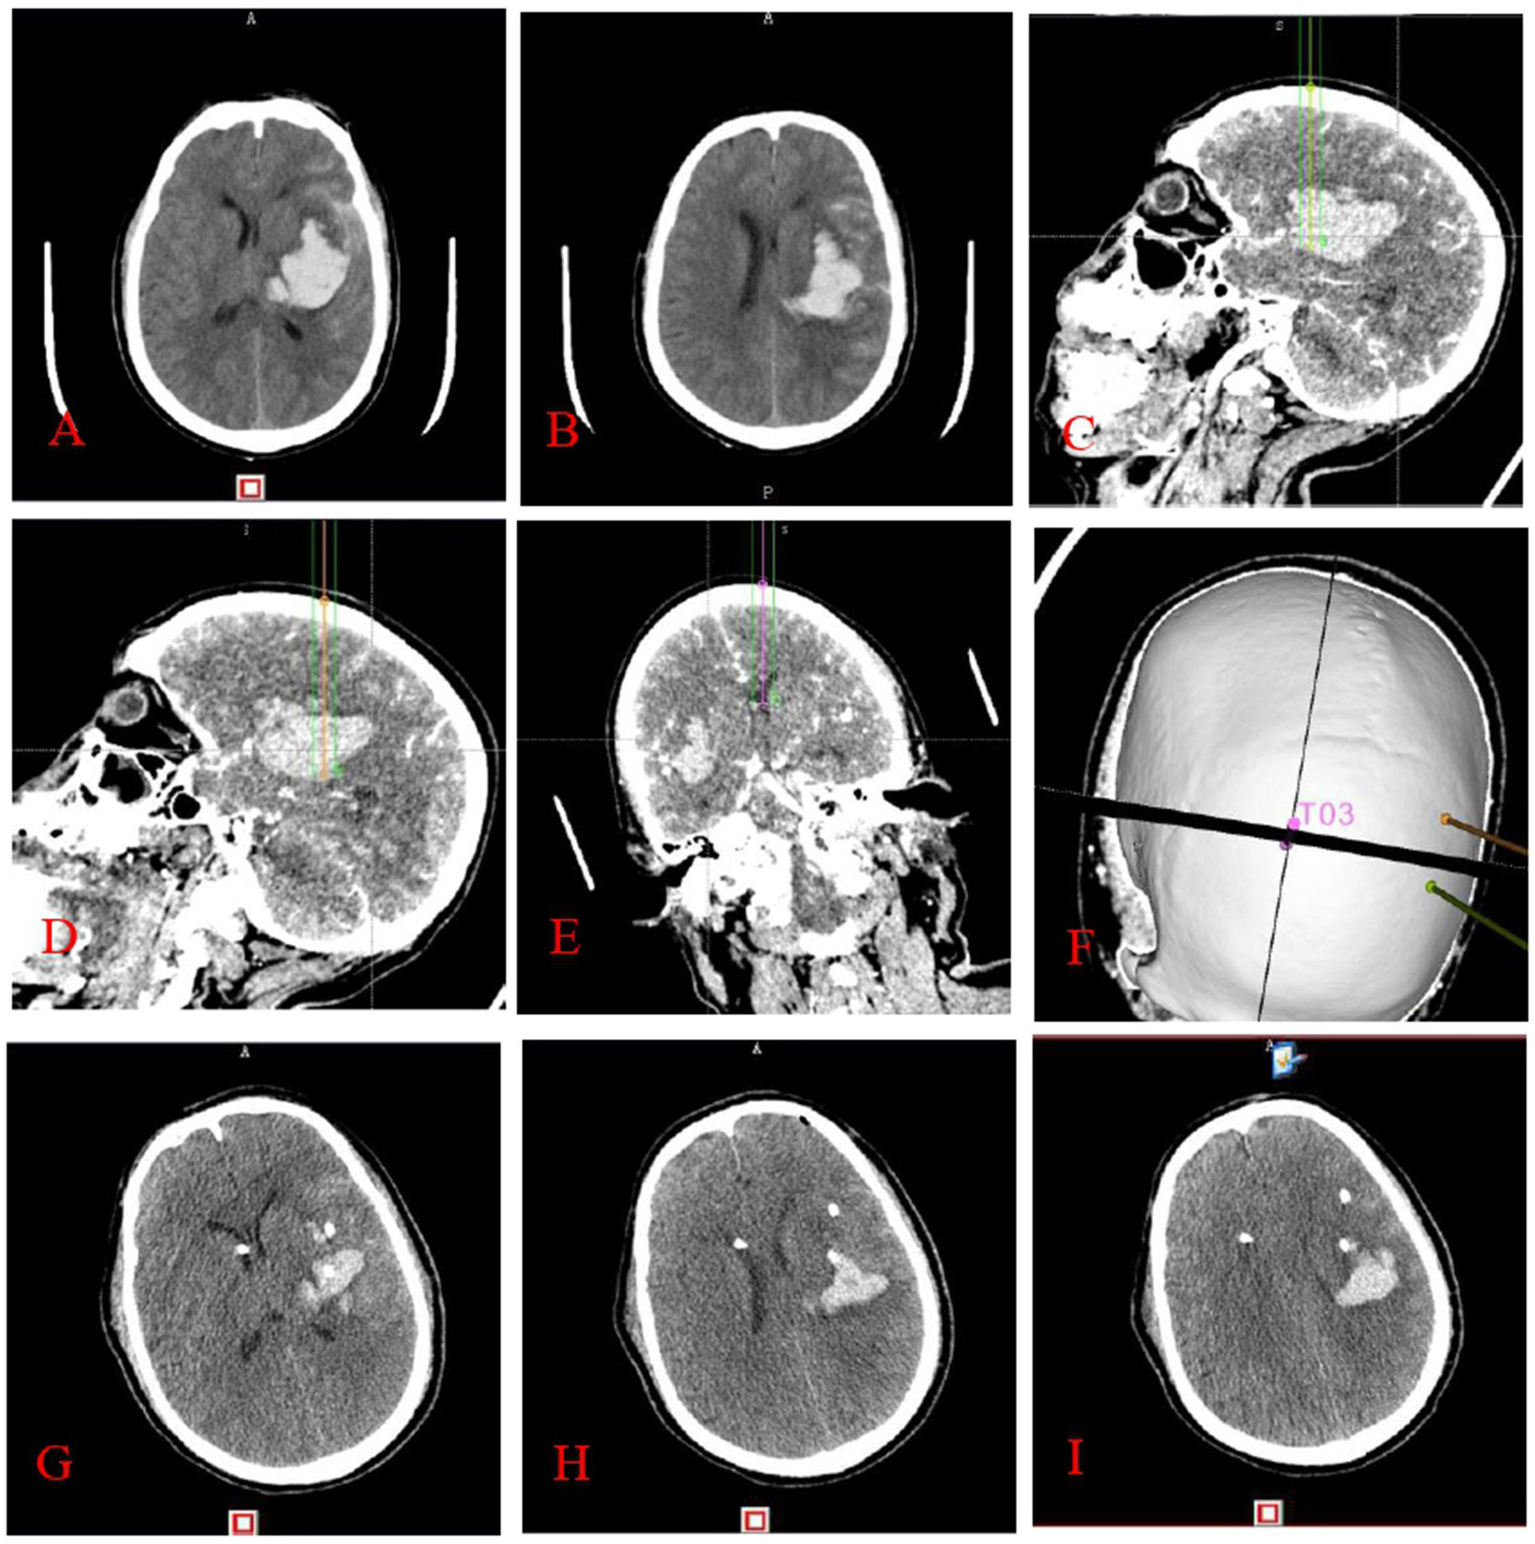

Figure 2

This figure illustrates stereotactic surgery conducted by the principle of cranial CTA angiography point sign: preoperative cranial CT (A,B) indicates a left basal ganglia hematoma. The surgical route design (C–F) utilized the anterior midpoint (C), posterior midpoint (D), and anterior horn of the right ventricle (E) of the hematoma as target areas, with puncture placement and drainage conducted with the aid of a neurosurgical robot. It is noteworthy that the dotted or striated hyperdense shadows depicted in images C–E correspond to angiographic points on the CTA, which are instrumental in the design of the surgical pathway. Three-dimensional reconstruction image of the puncture trajectory (F). Cranial CT (G–I) conducted within 24 h post-surgery indicates a substantial decrease in the hematoma.

Completion of stereotactic surgery guided by cranial CT: preoperative cranial CT (A,B) reveals a left basal ganglia hematoma. The surgical route design (C–F) involved targeting the anterior midpoint (C), posterior midpoint (D), and anterior pedicle of the right ventricle (E) of the hematoma, with puncture placement and drainage performed by a neurosurgical robot. Three-dimensional reconstruction image of the puncture pathway (F). Cranial CT (G–I) performed within 24 h postoperatively reveals an enlarged hematoma and hematoma formation around the drainage tube.